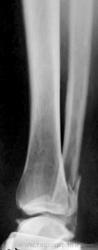

Пациентке 50 лет, в марте 2011 получила бытовую травму, при поступлению в одну из ЦРБ Нижегородской области был диагносцирован трехлодыжечный перелом, наружный подвывих стопы (рентгенограммы 1). Поскольку боковая рентгенограмма сделана с ротацией, никто не обратил внимания на передний отдел метаэпифиза б/берцовой кости. Пациентке налажено скелетное вытяжение (рентгенограммы 2,3), на боковом снимке видно повреждение переднего отдела метаэпифиза, но внимание на это не обращается, выполняется стандартный остеосинтез наружной и внутренней лодыжек (рентгенгограммы 4), опять же ни о кого не возникает никаких вопросов, а именно: почему дисконгруэнтна суставная щель, стопа в переднем подвывихе и в эквинусе. В августе пациентка приходит на контроль, и уже отчетливо виден дефект переднего отдела метаэпифиза б/берцовой кости, смещение костного фрагмента метаэпифиза кпереди и передний вывих стопы, но никаких мероприятий не проводится. Вчера, 9.02 пациентка все же доходит до нашего института, и мы видим такую картину (рентгенограммы 5,6): дефект переднего края дистального метаэпифиза б/берцовой кости, костный фрагмент смещен кпереди, некротизирован (фактически это секвестр), стопа в положении переднего вывиха, разрыв дистального межберцового синдесмоза, нестабильность металлоконструкций в б/берцовой кости (отчетливо видна резорбция), асептический некроз блока таранной кости. Прогноз неблагоприятен: артродезирование г/стопоного сустава, вопрос только в выборе метода, аппаратный артродез, либо ретроградный интрамедуллярный.

Уважаемые коллеги. Перелом отнюдь не краевой, а костный фрагмент был достаточных размеров. Подозреваю, что его  ошибочно посчитали  фрагментом заднего края. Остеомиелита ни клинически, ни рентгеологически не было. Даже если бы этот перелом и не был фиксирован, он мог бы сростись без дополнительной накостной фиксации, если бы стопа была выведена из переднего подвывиха и эквинуса, и иммобилизирована в положении тыльного сгибания. На данный момент помимо обширного дефекта переднего края есть и явления ассептического некроза блока таранной кости, восстановительная операция не показана, только артродез.